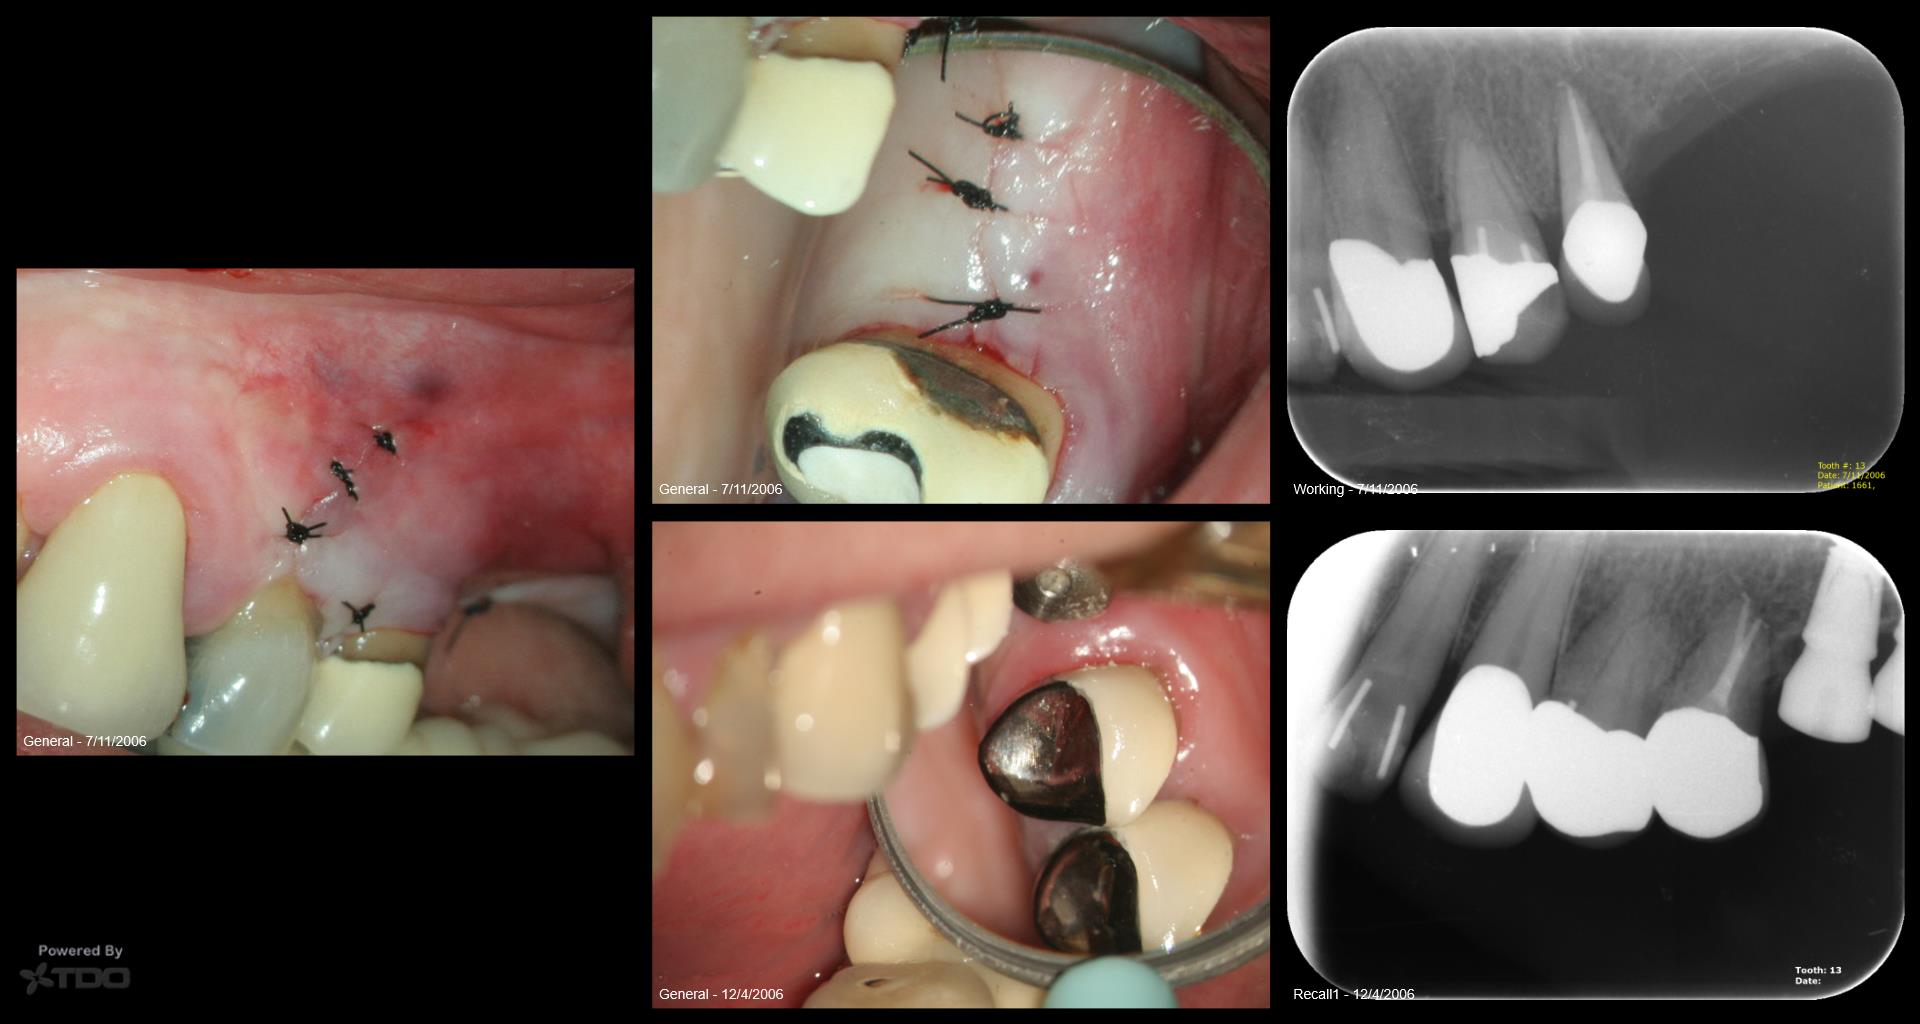

13 years on a tooth which shouldn’t have made it